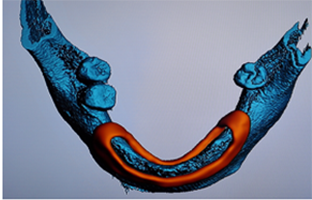

B.绘制下颌神经管

E.软件上修复体设计

C.添加模型数据

D.图像拟合

F.选择牙位添加种植体

G.选择合适的导环全程或者定位完成植体设计